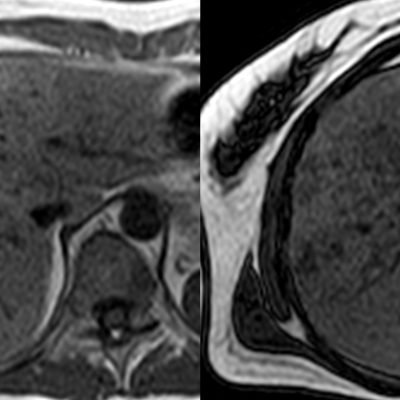

El estudio se complemento con resonancia magnética, donde se demostró la presencia de múltiples imágenes focales hepáticas confluentes con disminución de la señal en secuencias fuera de fase, no mostrando alteración de la señal en secuencias potenciadas en T2, sin signos de restricción al pulso difusión ni refuerzos anómalos luego de la administración de contraste endovenoso, estos hallazgos confirman la sospecha de esteatosis focal multinodular (fig. 5, 6 y 7).

En estos casos se recomienda realizar RM para confirmar la presencia de grasa en las “lesiones” identificadas y descartar otras etiologías, demostrando disminución de la señal en secuencias fuera de fase, sin alteración del pulso difusión (fig. 12 y 13).